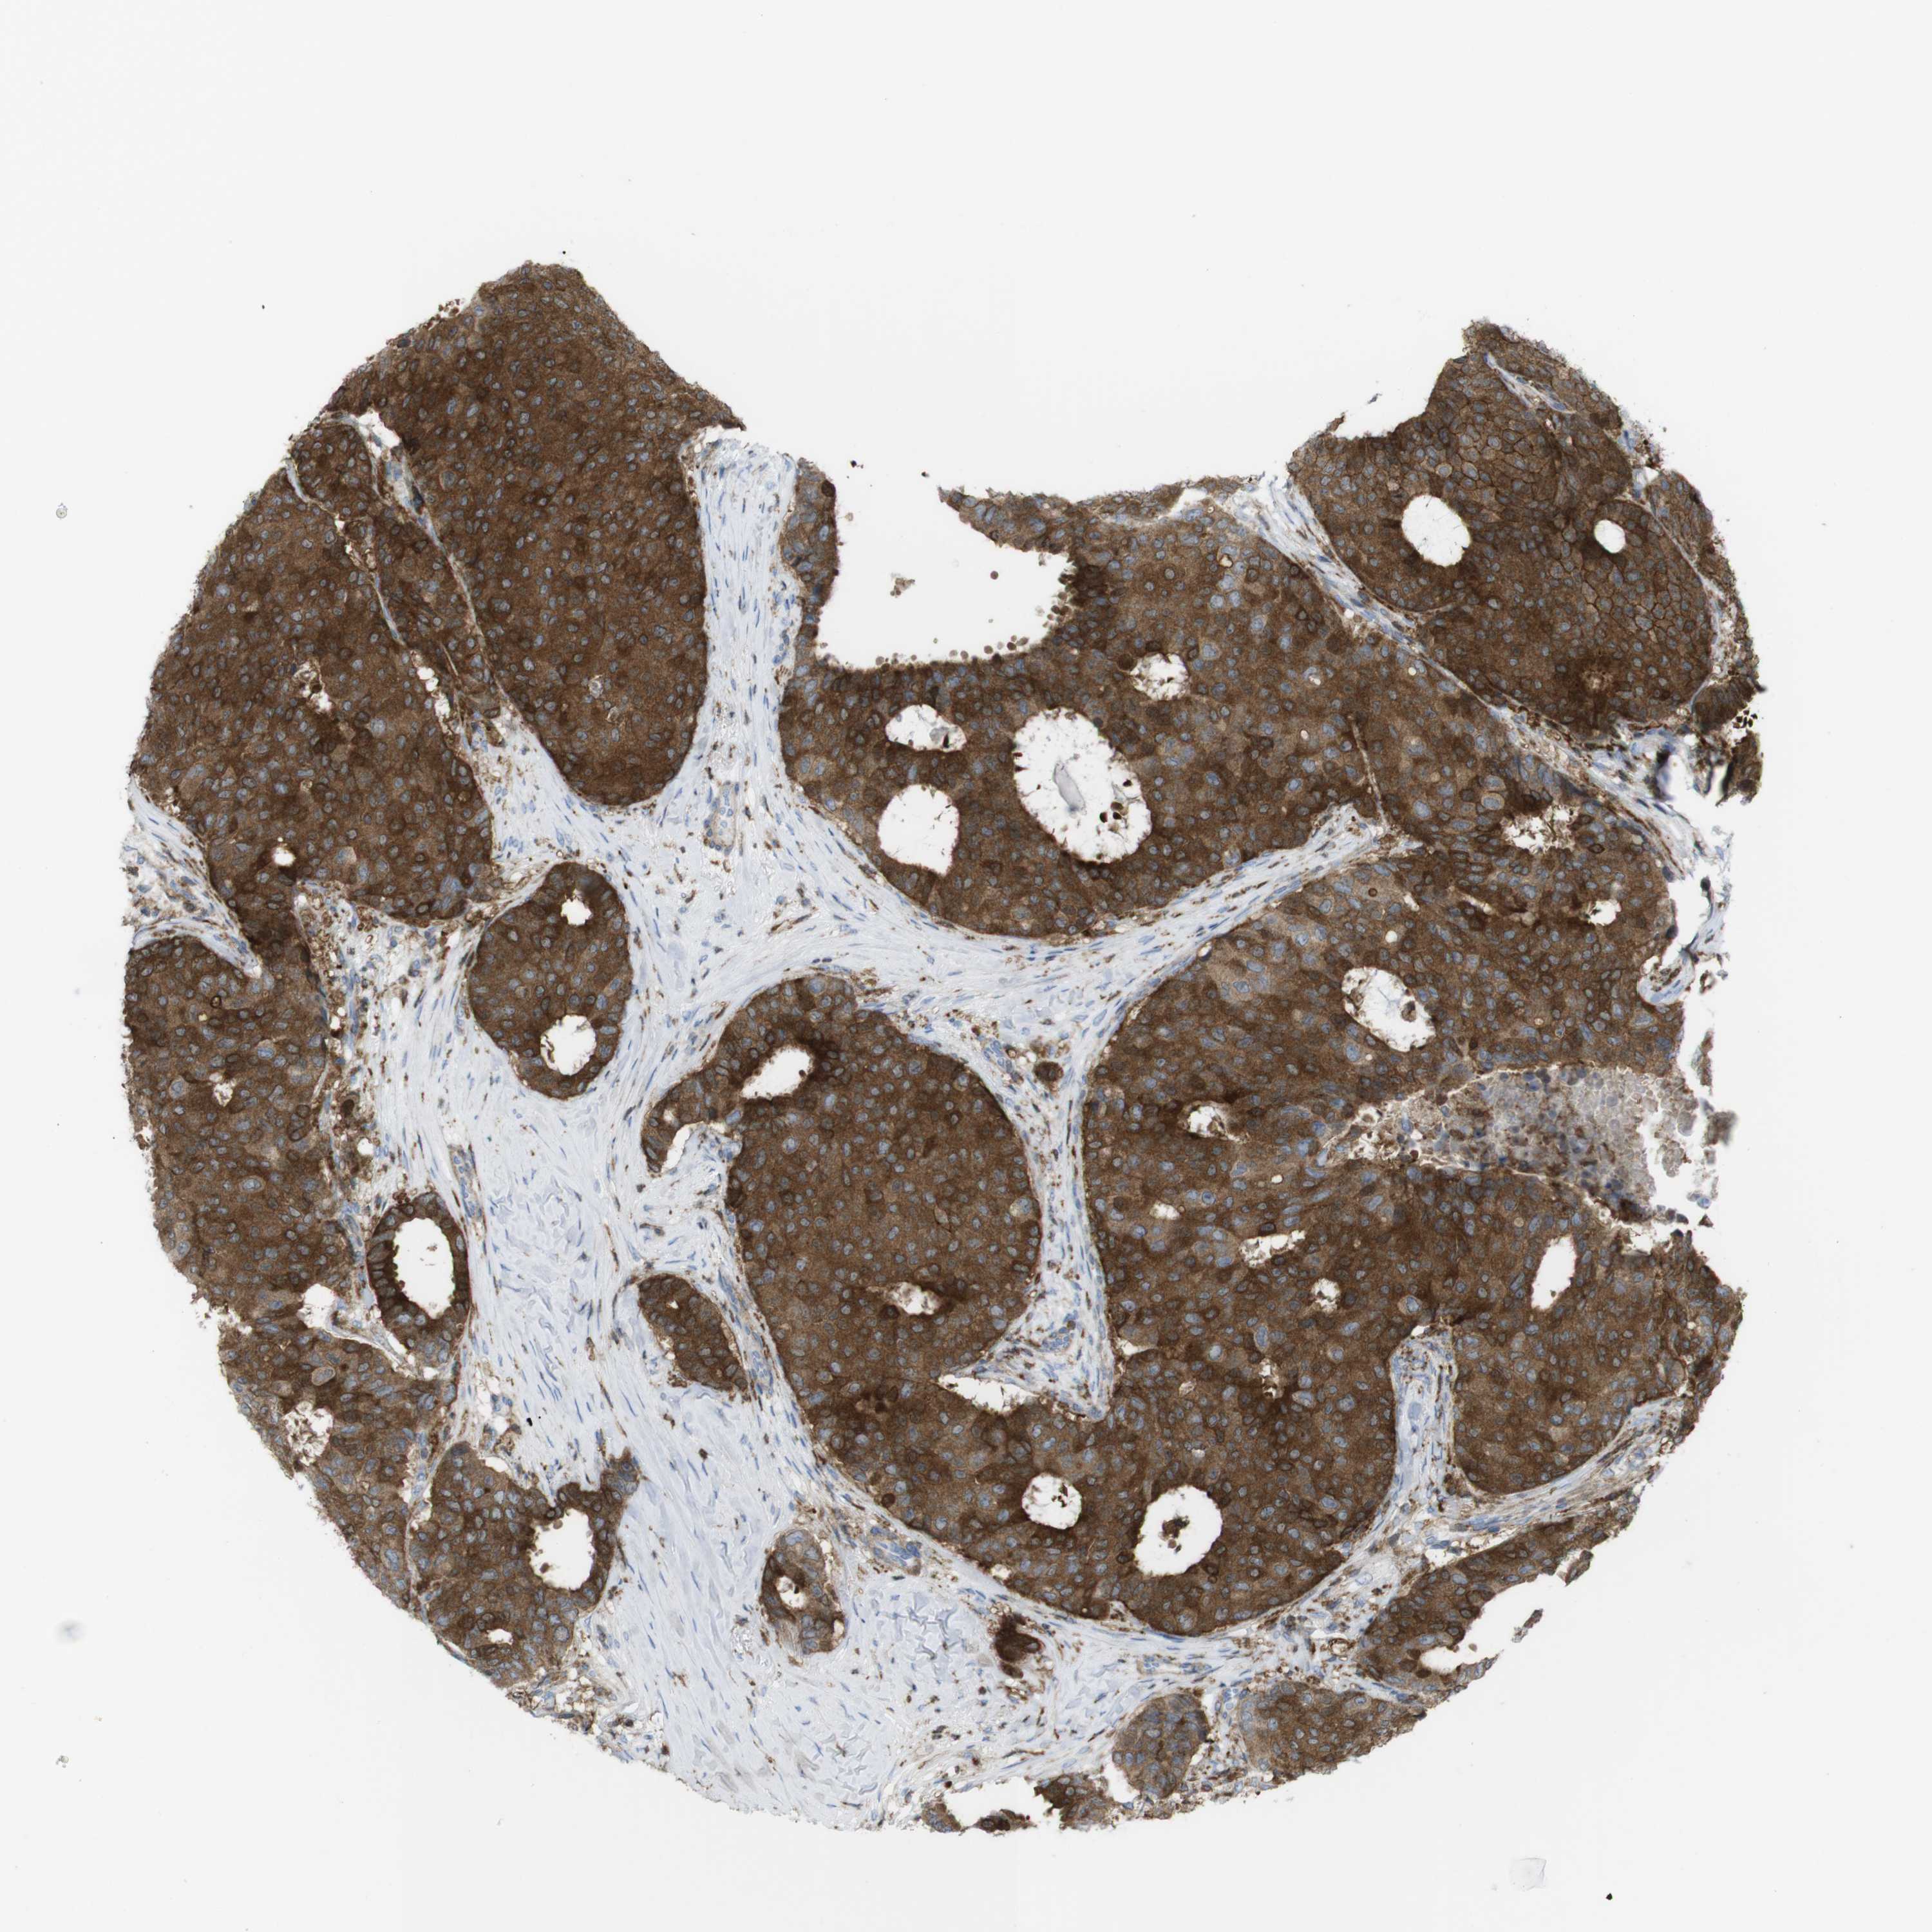

BRCA TCGA BRCA VALIDATION PROTEIN EXPRESSION